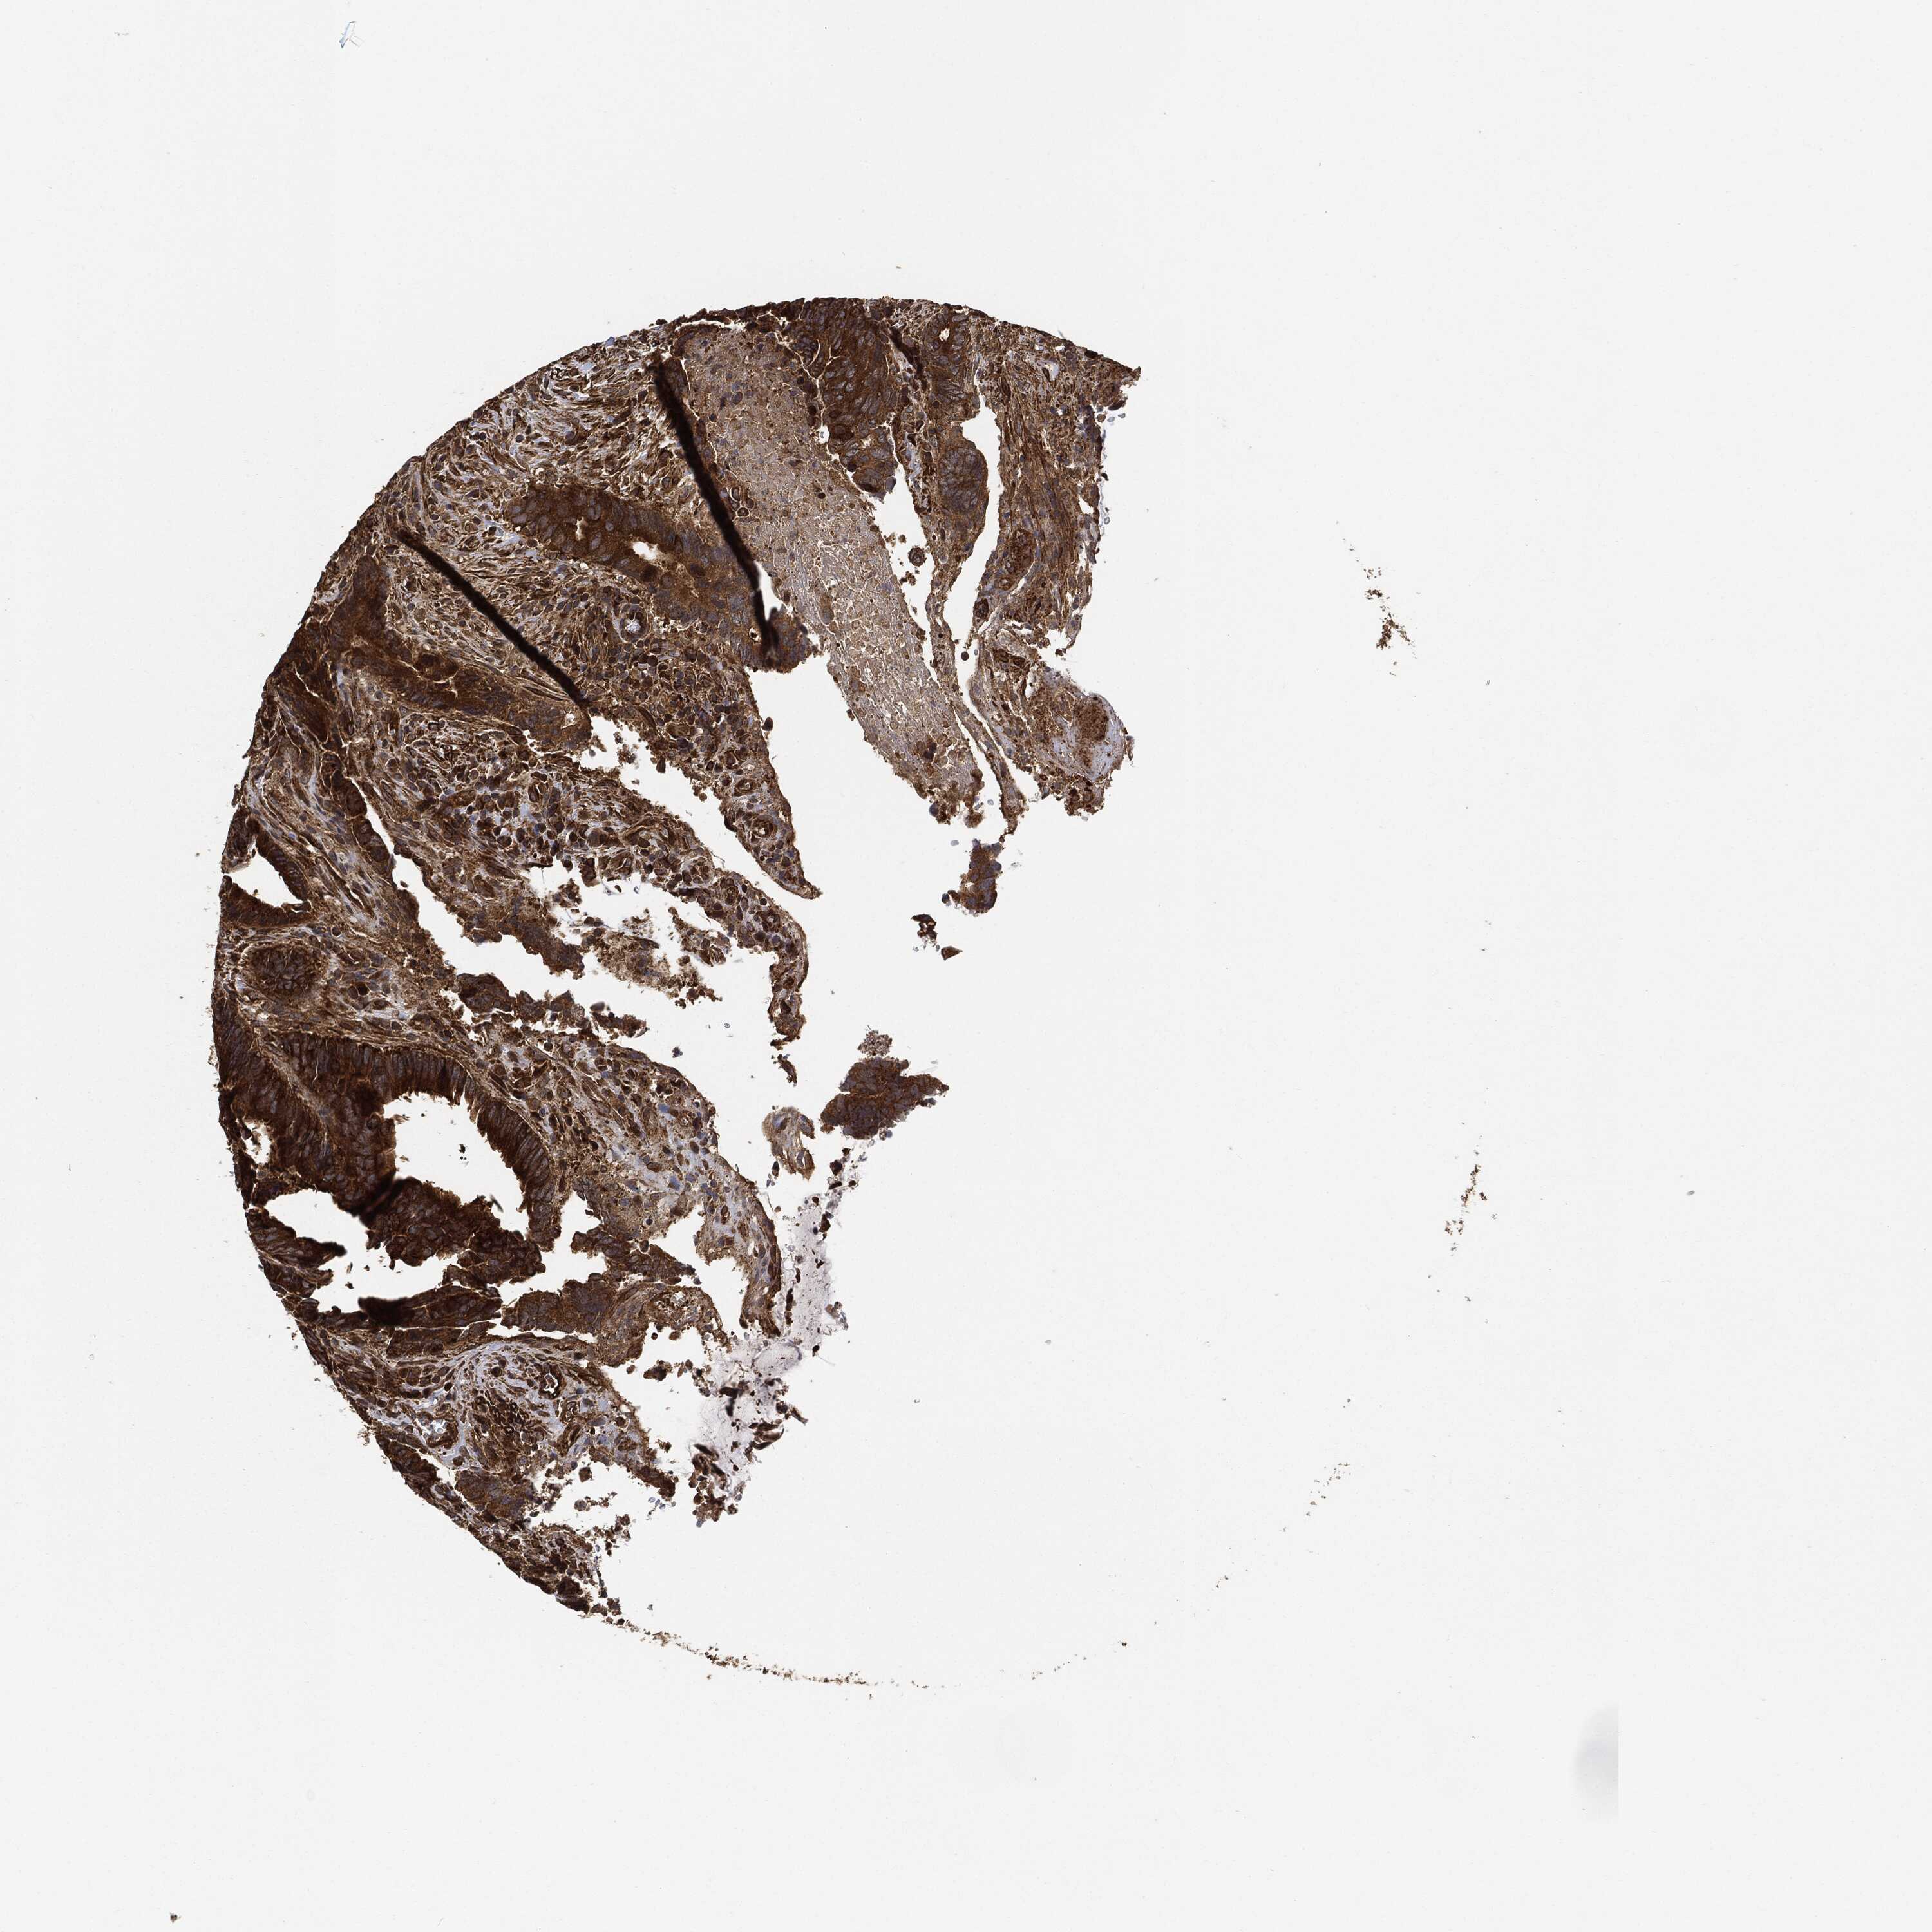

CANCER COLORECTAL CANCER Show tissue menu

Colorectal cancer

Human cancer

Colon adenocarcinoma